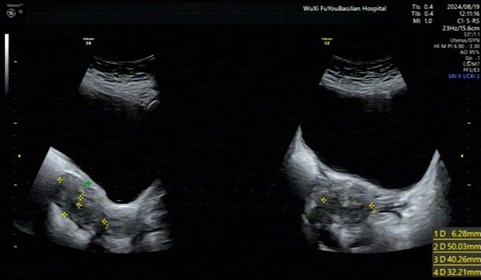

Postoperative follow-up: On August

19, 2024, the patient came to our hospital's outpatient department for

follow-up: CRP (panel), blood cell [five-category] analysis showed: basophil

percentage 1.1%, eosinophil count 0.66×10^9/L, basophil count 0.10×10^9/L, red

cell distribution width CV 15.6, platelet count 601×10^9/L, plateletcrit 0.42%.

Ultrasound examination: The uterus is anteverted, measuring 50×40×32mm, with

regular shape and clear contour. The myometrium of the uterus is uneven. The

endometrial thickness is 6mm, uneven (Figure

6).

Outpatient treatment with dienogest was prescribed. Currently, regular

follow-up is ongoing, and follow-up ultrasound, CRP, and blood cell tests are

all normal.

Figure 6: Follow-up ultrasound.